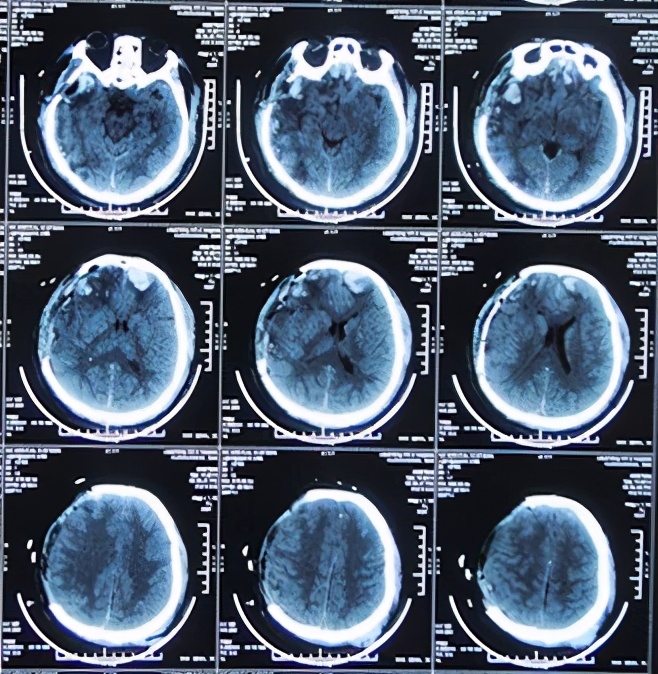

于2013年9月29日即开颅术后第12天(转院后第4天),转至北京某著名的某三甲医院,入院当日行头CT检查:脑膨出及脑肿胀均严重(图-4)。

图-4:2013年9月29日头CT

术后,患者减压窗张力持续偏高,并于2013年9月20日即开颅术后第3天,切口出现渗液红肿,给予抗感染及切口换药处理,并行切口分泌物细菌培养(注:2天后报告为阴沟肠杆菌生长)。于开颅术后第4天和第5天即2013年9月21日和9月22日两次行腰椎穿刺,均提示脑脊液压力升高明显。开颅术后第8天即2013年9月25日,行头CT检查:脑膜脑膨出较前加重(图-3),而且这期间头部切口感染仍进行性恶化,且体温升高至39℃以上、颈部僵硬,意识障碍逐渐加重等表现。

图-3:2013年9月25日头CT